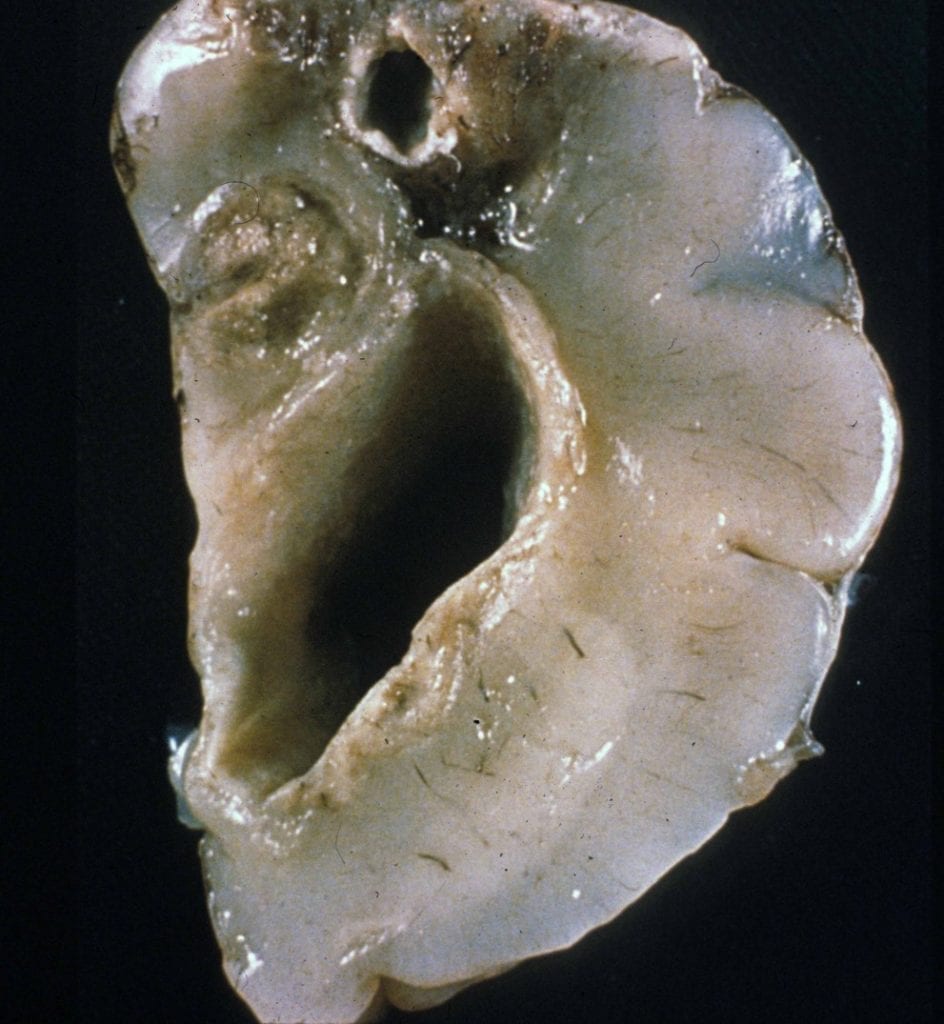

- Symptom onset between 2 months and 5 years with a loss of milestones, failure of brain growth, ataxia, myoclonus +/- seizures, and spastic paresis.

- Pathology with multinucleated giant cells and calcific vasculopathy (see below).

- MRI with diffuse atrophy.